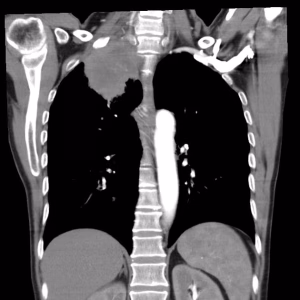

| Oboseala poate fi determinată de prezența unei formațiuni tumorale care obstruează căile aeriene, prezența de lichid în spațiul pleural (revărsat pleural) sau în pericard (foița care acoperă inima) purtând denumirea de pericardită, prezența a numeroși micronoduli și noduli distribuiți aleatori în ambele campuri pulmonare care ar putea să ridice suspiciunea unei carcinomatoze pulmonare și nu în ultimul rând prezența unei pneumonii retrostenotice sau atelectazii [căile respiratorii sau saculeții cu aer (alveolele) nu se mai pot dilata]. Pentru evaluarea dispneei se utilizeză scala Borg și mMRC. | |

- Simptome date de diseminarea intratoracică: revărsat pleural, revărsat pericardic, chilotorax (prezența de lichid pleural ca urmare a unei obstrucții la nivelul canalului limfatic), disfonie (compresiunea/invazia nervului laringeu recurent), disfagie (compresiunea/invazia esofagului), sindrom de venă cavă superioară (cefalee, edem în pelerină, venectazii și cianoză), sindromul Claude – Bernard – Horner (ptoza palpebrală, enoftalmie, mioză) și tumora Pancoast – Tobias (prezența unei formațiuni tumorale care erodează arcul costal și invadează plexul brahial de aceeași parte – homolateral, cu apariția unui sindrom algic și atrofierea musculaturii membrului superior).